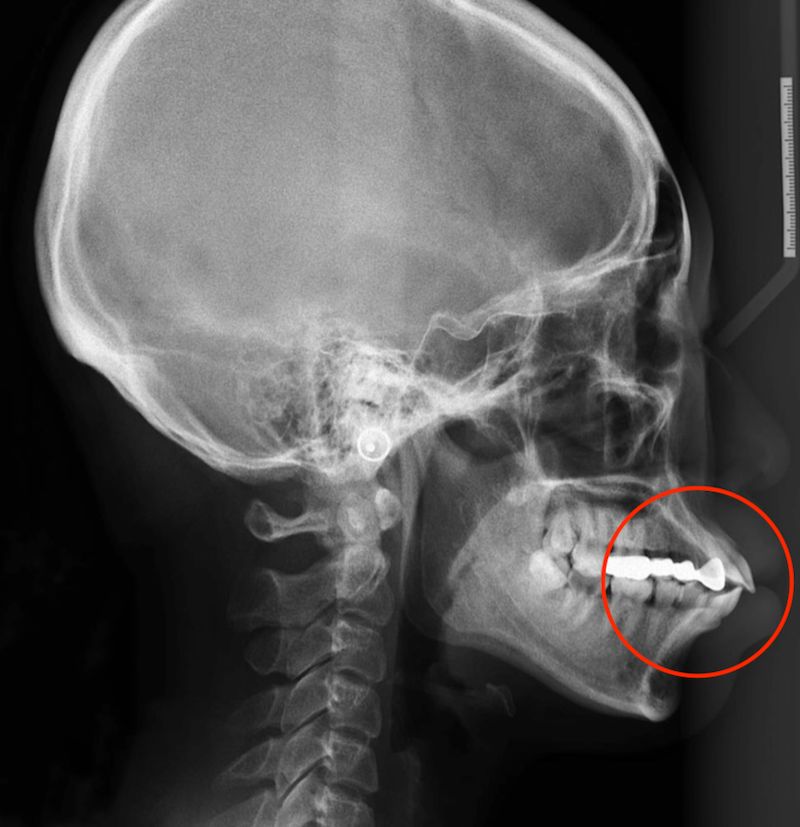

齿槽型嘴突主要表现为:牙槽局部突出,前牙唇倾。

齿槽型嘴突

对于牙性嘴突,常见的治疗方案是:拔除四颗前磨牙,利用拔牙的间隙回收前牙,改善前突问题。